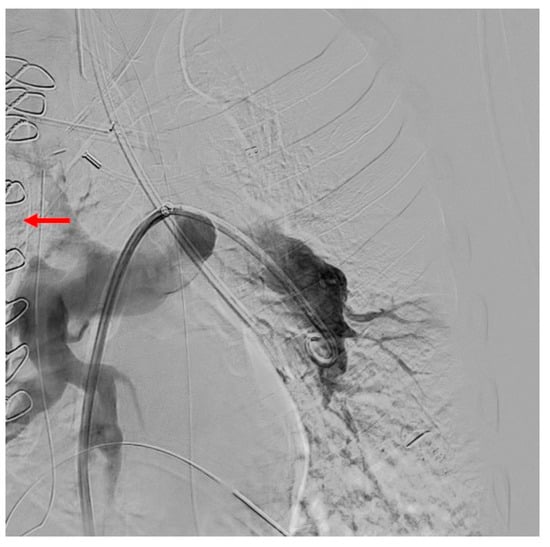

3.4. Computed Tomography Pulmonary Angiography (CTPA)